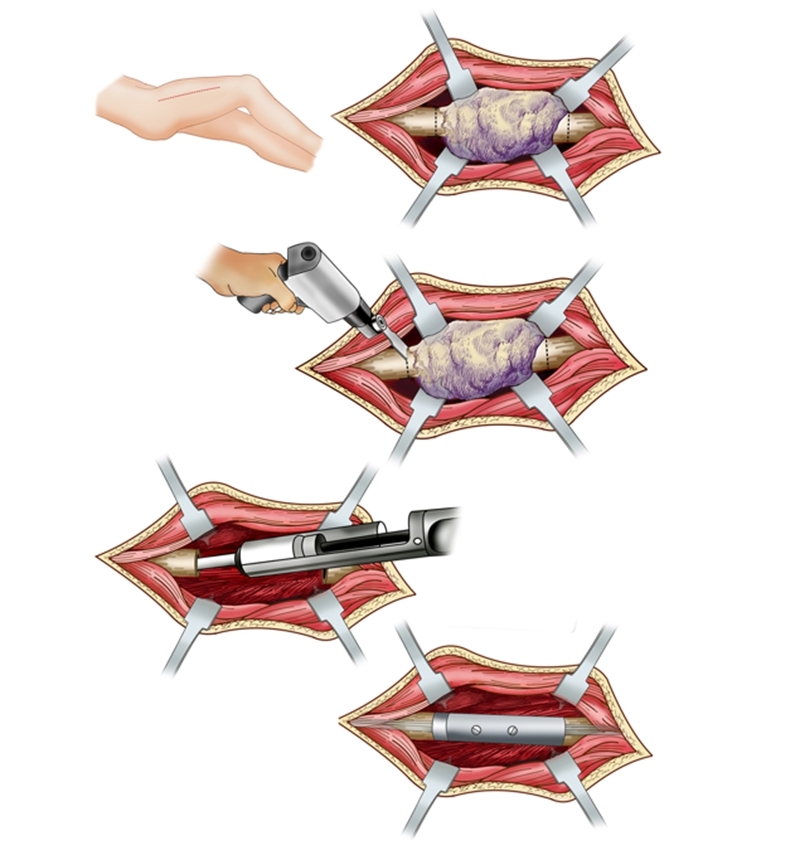

为进一步解决骨干肿瘤诊治中的难题,胡永成教授通过多年临床研究,终于设计出“骨干组配式假体”,该技术通过较小的创伤便可使患者得到好的治疗效果。除此之外,胡永成教授还根据骨干肿瘤发病部位的不同进行分区,根据不同的损伤部位可以进行个性化假体的选择,不仅可以帮助患者保留关节,患者术后还能即刻下地,大大减轻了肿瘤患者的痛苦,并提高了生存质量。

骨干组配式假体展示

分区

病例分享

患者女性,68岁,乳腺癌病史,右股骨中段病理性骨折,股骨长段溶骨性破坏,并有跳跃病灶。病变的长度为16cm,病灶近端在小转移水平,因为近端髓腔柄较短,故选择A区骨干假体。经病理诊断为转移性腺癌,术后2周患者拆线后即可离床活动。